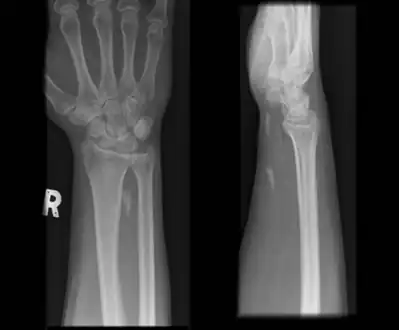

Radiographs of wrist demonstrating Calcific tendonitis of flexor carpi ulnaris.